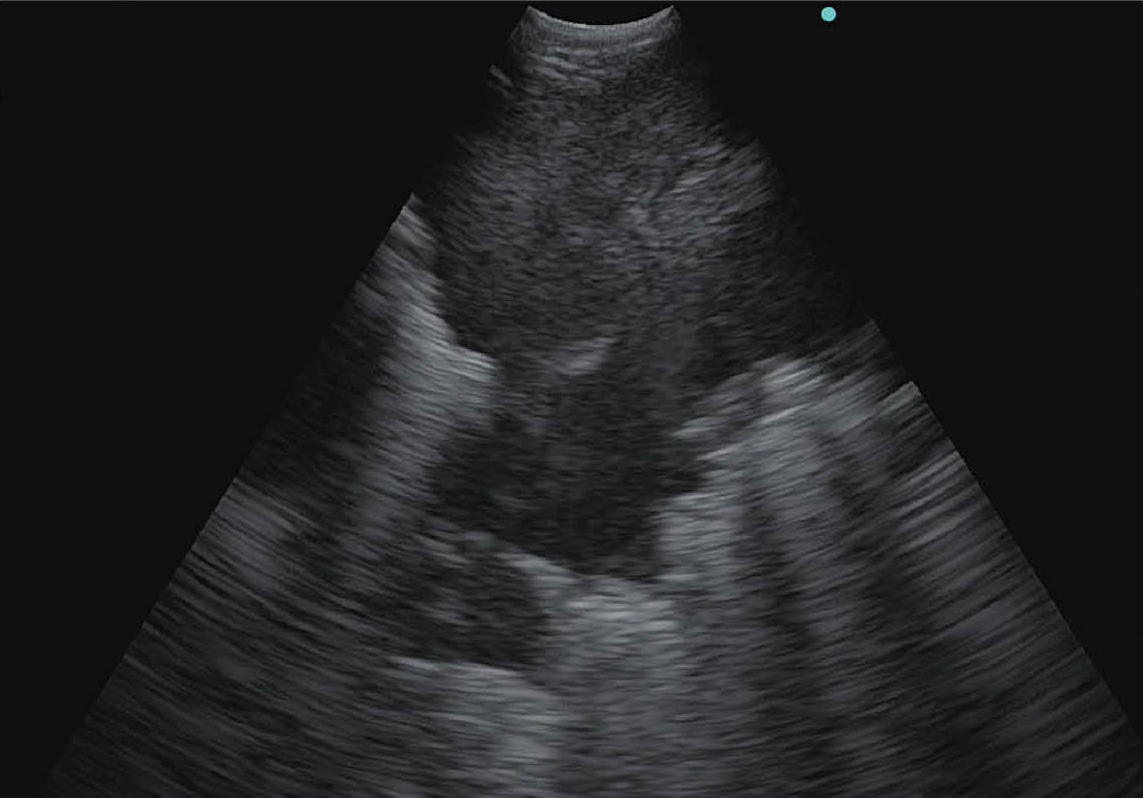

CHE 模式

將超音波造影劑的散射訊號影像化,使組織內的血流更容易觀察。(左:EU-ME2、右:EU-ME3)